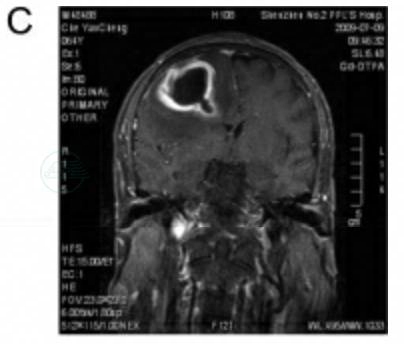

病例C

患者王某,男性,47岁。

主诉:反复头痛1月余,发现右侧跛行伴不能言语1周。

现病史:患者于1个月前即反复出现头痛,当地门诊为“上感”,予对症处理,间断性缓解。1周前无明显诱因出现右侧肢体无力,跛行,并逐渐不能言语。行CT后,以左颞叶占位病变收入院。起病前无发热史。吸烟20余年,约20支/天。

入院后行MRI见左颞叶占位,周围水肿明显,内有坏死组织,边缘可见环形强化,考虑恶性胶质瘤,转移癌待排(图5)。胸片、腹部B超未见异常。血常规结果正常。入院后急诊行左颞叶占位切除术,术中冰冻考虑“转移癌”,予切除肿瘤后去骨瓣减压。

图5 病例3MRI扫描